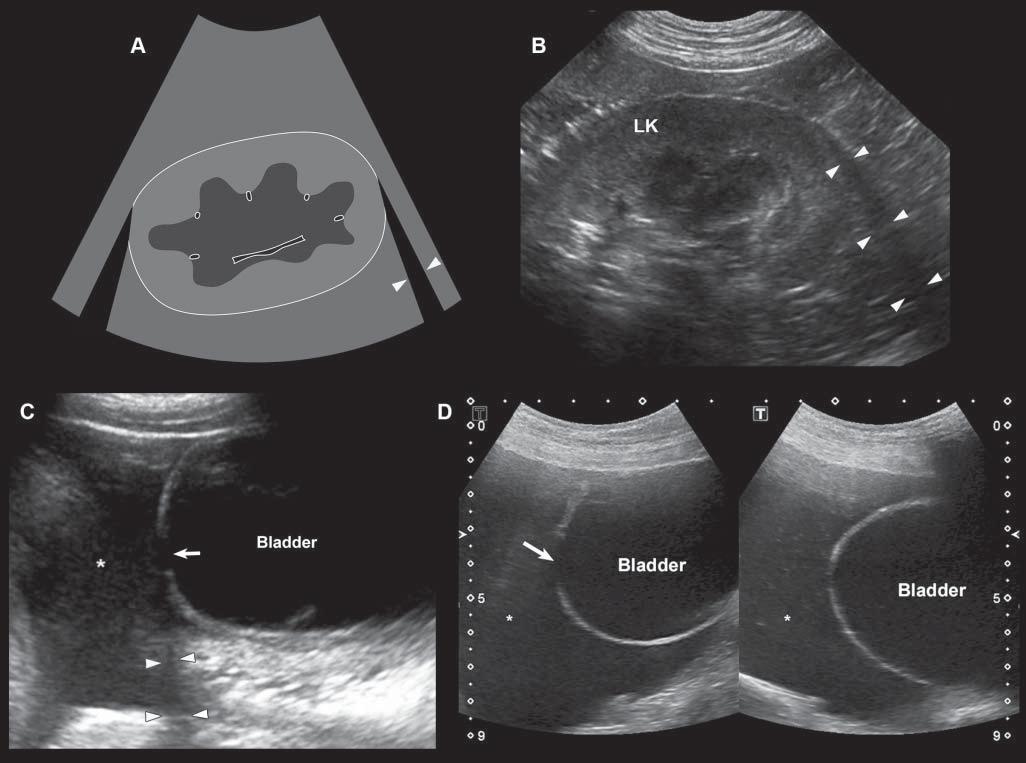

Edgeshadowing appearsasdiscrete,triangular zonesoflowamplitude,attheedgeofacurved structure(Figure1.14A).When,thecurvedstructure isfluidfilled,theedgeshadowingartifactbordersthe enhancementartifact.Thistypeofrefractiveshadowingcanbeconfusing,especiallywhenitoccursatthe

cranialaspectofafluidfilledbladder,andappearsas a“defect”ofthewall(Figure1.14B).

Figure1.14. Edgeshadowingandrefraction.A,B: Edgeshadowing(arrowheads)isoftenseeninprolongationoftherenal pole.LK,leftkidney. C: Thecurvatureofthebladderwallcausesbeamrefraction,whichresultsinanacousticshadow(arrowheads)inthisdogwithechogenicperitonealeffusion(*).Aholeinthebladderwall(arrow)isartifactuallycreated. D: Inanother dogwithcardiactamponadeandmarkedperitonealeffusion(*),theartifactualholeinthebladderwall(arrow)isattenuated byrepositioningthetransducerwithadifferentangulation.